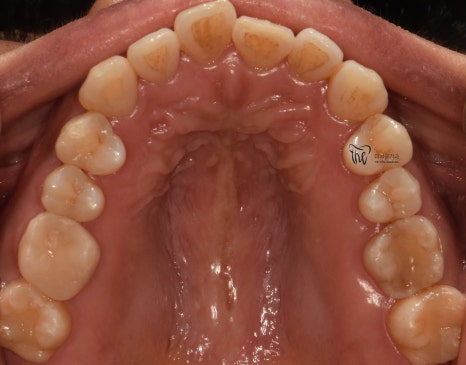

교합면에서 봤을 땐, 교정치료를 떠나서

선행해야 될 치료들이 많다는 것을 알 수 있습니다.

아말감이 수복 되어있던 곳의, 아말감 탈락에

따른 치질이 드러나 있다던지, 교합면의

다발성 우식증에 따라서 충치치료도 같이

병행을 해야 되는 상황입니다.